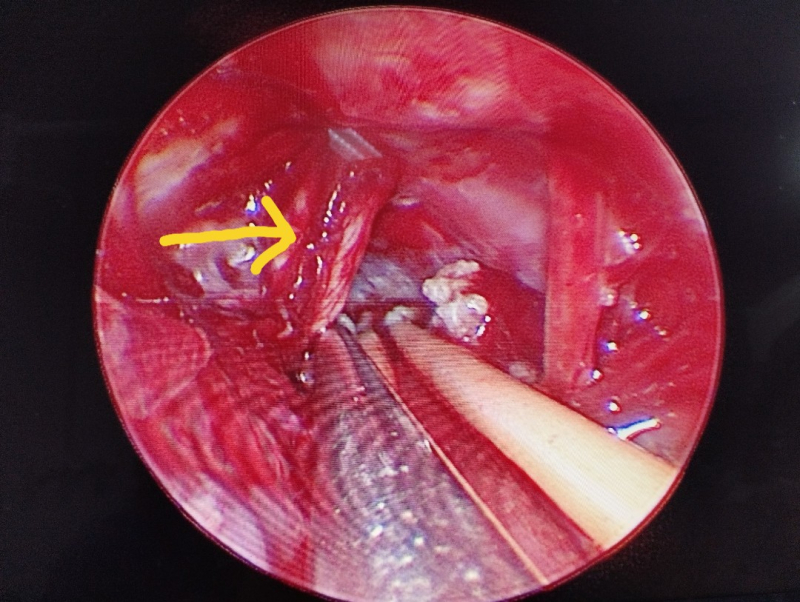

Xung đột mạch máu và thần kinh V trên hệ thống nội soi

Dưới sự hỗ trợ của hệ thống phẫu thuật vi phẫu và nội soi hỗ trợ, Ekip phẫu thuật của Ths.BS Giang Lộc Anh (Khoa Ngoại – Thần kinh lồng ngực, Bệnh viện Bãi Cháy) đã tiến hành mở xương sọ sau xoang sigma, lấy u tối đa, giải ép xung đột mạch máu - thần kinh V. Ca phẫu thuật diễn ra an toàn, đảm bảo cầm máu tốt và bảo tồn cấu trúc não lành và các dây thần kinh quan trọng. Sau 7 ngày, bệnh nhân phục hồi tốt, giảm đau rõ rệt, không ghi nhận biến chứng và được xuất viện.

Hiện nay, với sự hỗ trợ đắc lực của các trang thiết bị hiện đại như hệ thống vi phẫu, hệ thống nội soi, phẫu thuật viên có thể quan sát phẫu trường vùng góc cầu – tiểu não, vùng gần thân não, các vị trí xung đột mạch máu – thần kinh dưới nhiều góc độ hơn, rõ ràng hơn. Nhờ đó kiểm soát trường mổ tốt, tránh gây tổn thương vùng não lành và các dây thần kinh, hạn chế biến chứng sau phẫu thuật như dò dịch não tủy, ù tai, điếc, liệt mặt..., giúp người bệnh hồi phục sức khỏe nhanh chóng”.